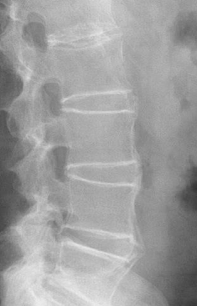

Rotation Lateral L-Spine

Separated posterior vertebral bodies

Spinous process shifted to the right of midline = slight LPO

Tilt (or ____) Lateral L-Spine

Sagging

Indicated by closed intervertebral foramina and joint spaces

To fix rotation on a lateral L-spine, ensure the ____ are stacked. To fix tilt or sagging, place a _____ under the patient's waist.

Hips and shoulders

Support sponge